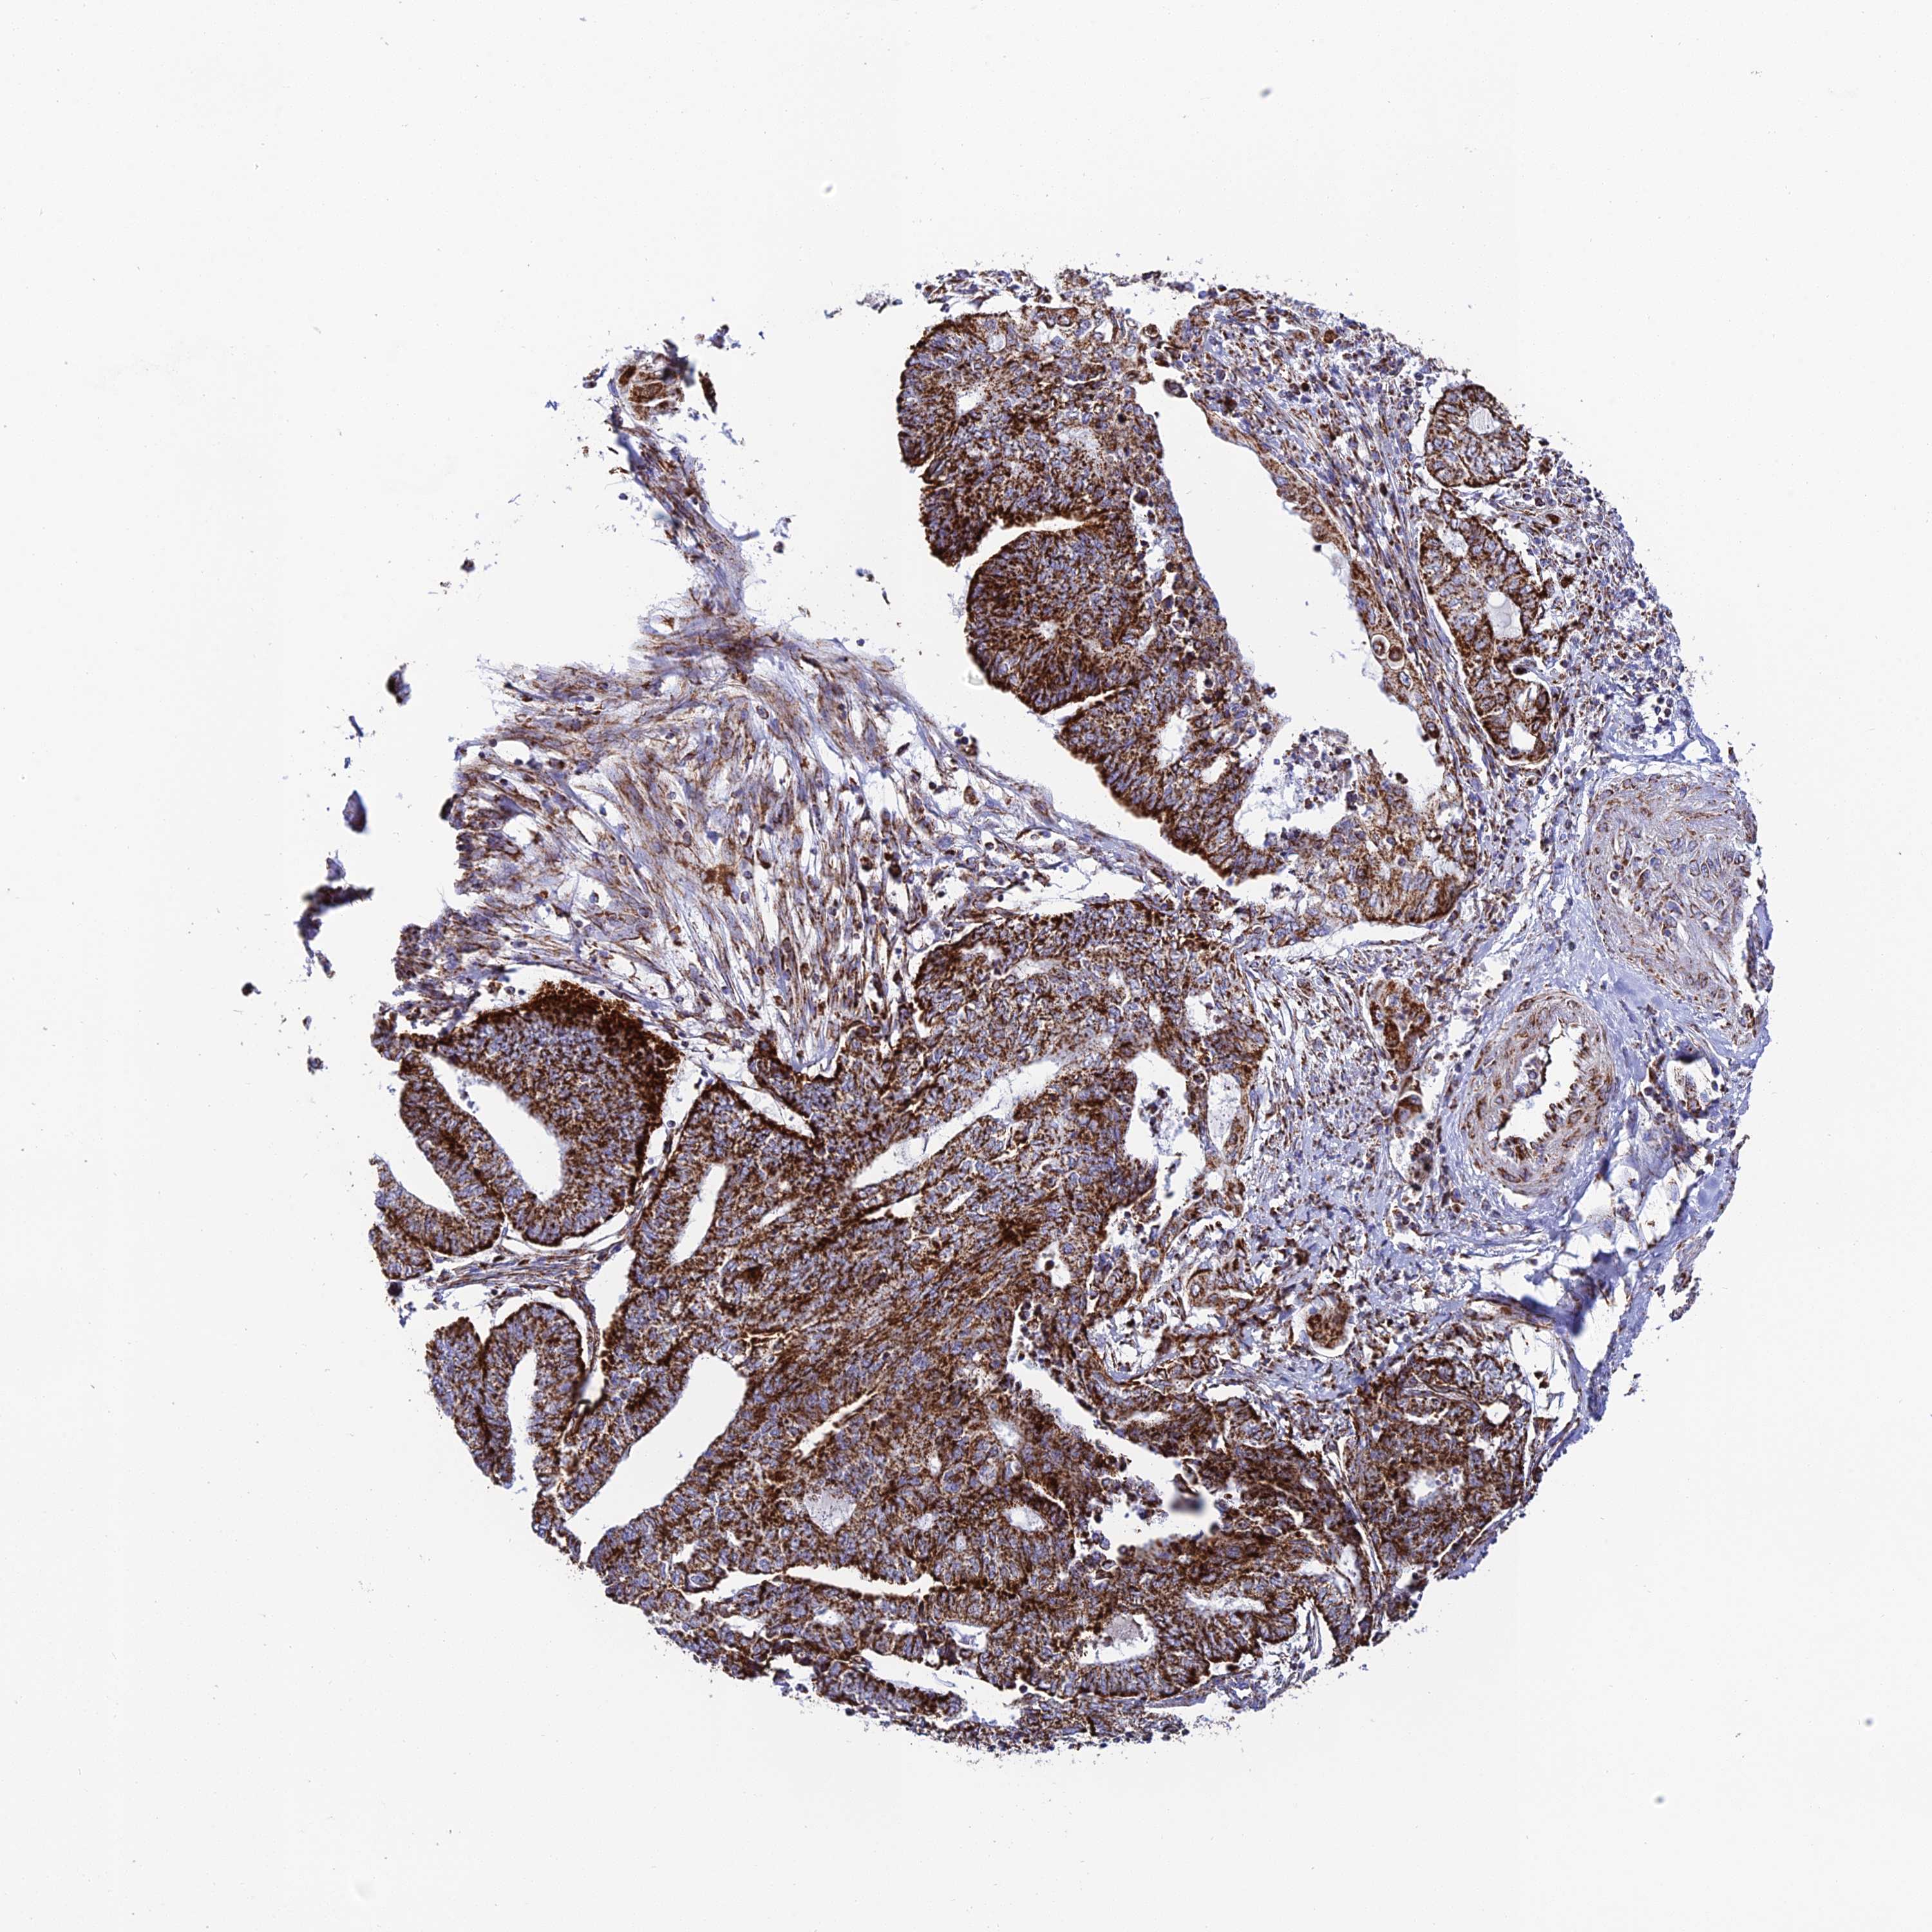

ENDOMETRIAL CANCER - Protein expressioni

A mouse-over function shows sample information and annotation data. Click on an image to view it in a full screen mode. Samples can be filtered based on level of antibody staining by selecting one or several of the following categories: high, medium, low and not detected. The assay and annotation is described here.

Note that samples used for immunohistochemistry by the Human Protein Atlas do not correspond to samples in the TCGA dataset.

Antibody stainingi

Antibody staining in the annotated cell types in the current human tissue is reported as not detected, low, medium, or high, based on conventional immunohistochemistry profiling in selected tissues. This score is based on the combination of the staining intensity and fraction of stained cells.

Each image is clickable and will lead to virtual microscopy that enables deeper exploration of all samples and also displays staining intensity scores, fraction scores and subcellular localization as well as patient and tissue information for each sample.

Antibody HPA042935

Staining

High

Medium

Low

Not detected

Intensity

Strong

Moderate

Weak

Negative

Quantity

>75%

75%-25%

<25%

None

Location

Nuclear

Cytoplasmic/membranous

Cytoplasmic/membranous,nuclear

Adenocarcinoma, NOS

Adenocarcinoma, metastatic, NOS